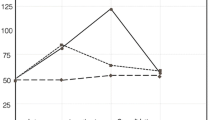

Quantitative immunohistochemistry was performed to investigate the effect of TP508 injection on the total number of cells and on the number of differentiated bone cells in the central area of the gap. The total number of cells (immunostained and unstained) in the ROI was not significantly different between the three groups. Mean values and the standard deviation of the total number of cells in the tissues treated with 0, 30 μg TP508 and 300 μg TP508 were 958±217, 1140±137 and 1161±282, respectively (ANOVA, P=0.5). This indicated that TP508 injection had no overall effect on total number of cells in the distraction gap. Next, we counted the number of cells, in the ROI, expressing each of the three antibodies tested. Absolute values of immunopositive cells in the 0, 30 μg TP508 and 300 μg TP508 groups were as follows: for Runx2, 263±61, 288±171, 560±115, respectively; for OPN, 299±201, 244±40, 677±216, respectively; for BSP, 255±111, 252±73, 480±31, respectively. We also expressed the number of immunopositive cells as a percentage of the total number of cells (Fig. 4). The number of Runx2- and OPN-expressing cells was significantly higher in the group treated with 300 μg TP508 than in the control group that received only saline (P<0.05; Fig. 4). The number of BSP-expressing cells was also higher in the 300 μg TP508 group than in the 30 μg TP508 group (P<0.05). No significant differences were found between the 30 μg TP508 group and the control group receiving saline (P>0.05).

Effect of TP508 injection on the number of immunopositive cells in the central portion of the distraction gap (black bars Runx2-positive cells, grey bars OPN-positive cells, white bars BSP-positive cells). Data are presented as percentage cells immunopositive for each of the three proteins examined (means±SD). *The percentages of Runx2-, OPN- and BSP-positive cells in the 300 μg TP508 group were significantly higher than for cells with the corresponding proteins in the saline-treated control group; the percentage of BSP-positive cells in the 300 μg group was also significantly higher than that in the 30 μg group (ANOVA, P<0.05)

The previous data suggested that TP508 increased the differentiation of osteogenic cells into osteoblasts in situ. To determine whether TP508 had any direct effect on osteogenic cells that were in the process of turning into osteoblasts, we performed in vitro experiments with the (mouse) osteoblast-cell line MC3T3-E1 after pre-culture in the presence of dexamethasone. After a 24-h stimulation with TP508, we found a significant (but slight) downregulation of Runx2 mRNA at 10 μg/ml TP508 (P=0.008) but no change at 100 μg/ml TP508 (Fig. 5).

Quantitative reverse transcription/polymerase chain reaction analysis of Runx2 mRNA expression in mouse osteoblast-like (MC3T3-E1) cells cultured for 24, 48 and 72 h in the presence of TP508 (black bars control group with 0 μg/ml TP508, hatched bars 10 μg/ml TP508, white bars 100 μg/ml TP508). Data are presented as means±SD (n=8) and are representative of two experiments. *The 10 μg/ml TP508 group at 24 h of incubation was significantly lower than the control group (one-way ANOVA; Tukey’s multiple comparison test, P<0.01). Correlation analysis between mRNA and culture time: r2=0.94, P=0.06 for 10 μg/ml TP508; r2=0.99, P=0.06 for 100 μg/ml TP508